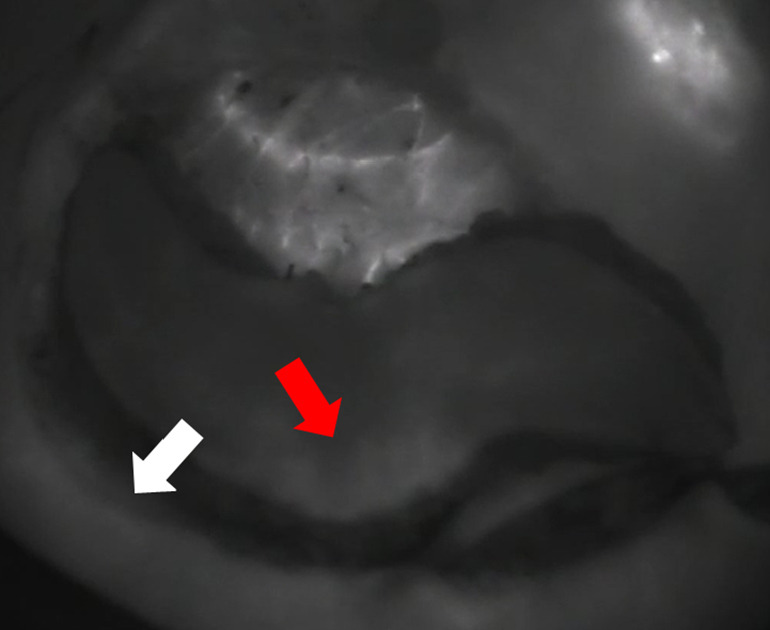

Results: Eight patients had anterior intercostal artery perforator (AICAP) flap reconstruction. Thirteen patients had lateral intercostal arterial perforator (LICAP) flap reconstruction with or without lateral thoracic arterial perforator (LTAP) flap reconstruction. One patient had thoracodorsal arterial perforator (TDAP) reconstruction. The ICG was used in 21 flaps. ICG perfusion was completed within 2 minutes (range, 20-110 seconds). Most of the patients had two perforators identified by ICG. In 88% of cases, ICG perfusion of the perforator flap and adjacent normal tissue was visualized simultaneously. There was a difference in ICG perfusion onset time between flaps with one versus multiple perforators.

Conclusions: ICG angiography can be used intraoperatively for flap assessment with helpful information. A perfusion time of less than 2 minutes was correlated with a good clinical outcome. Intraoperative ICG angiography can guide surgeons in evaluating flap perfusion, which can help address both immediate and long-term morbidity concerns.